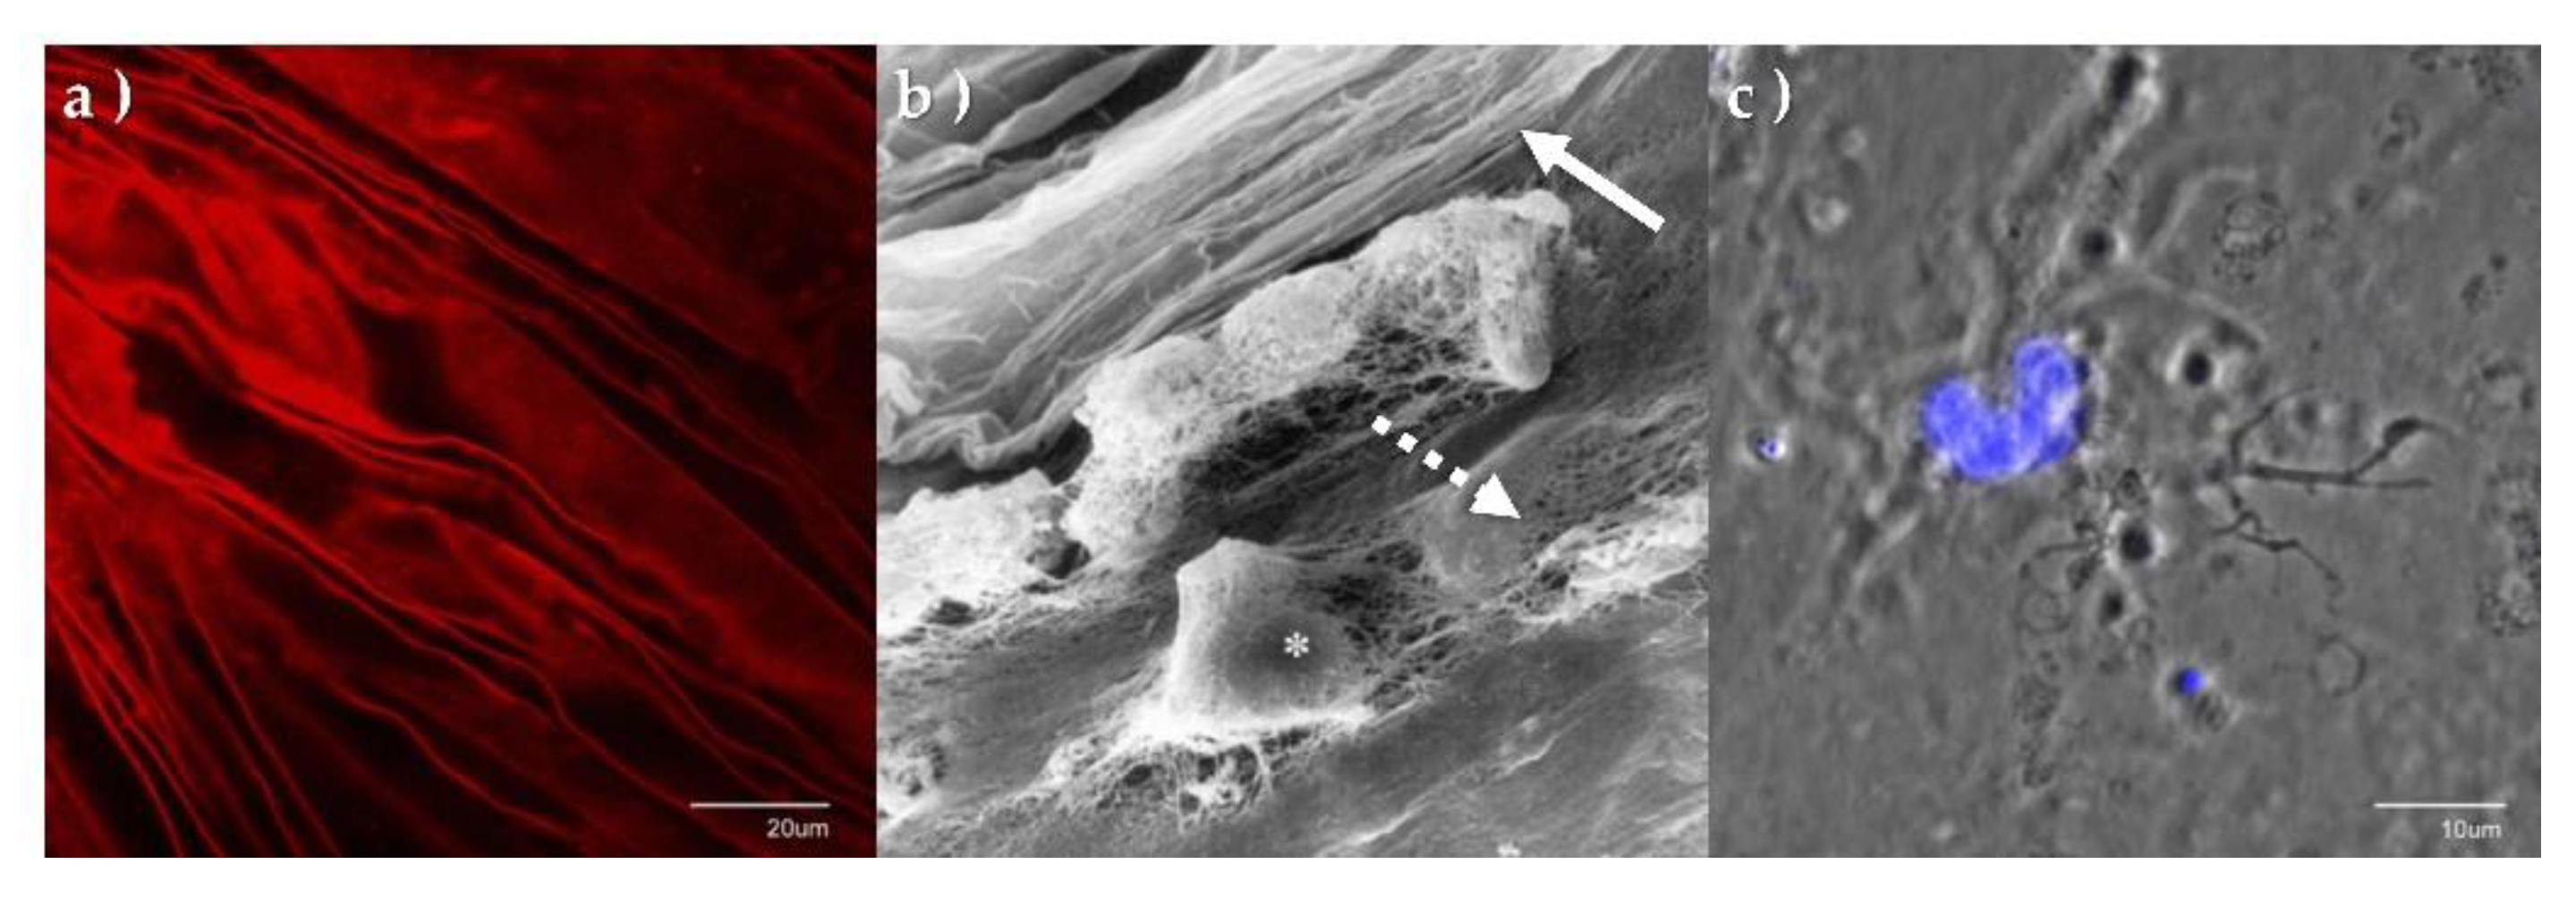

6. The Laminocyte